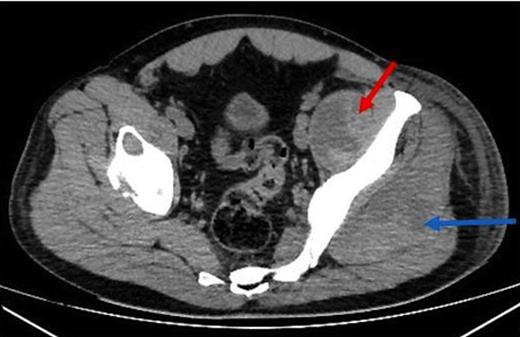

The patient underwent a Doppler scan which ruled out a DVT, then a CT scan of the left hip and thigh (figure 2). This demonstrated generalised superficial oedema with a small collection over the lateral thigh, and an irregular low density appearance of the gluteus and psoas muscles. With progressive deterioration in clinical state, the patient underwent ultrasound scanning of the thigh and hip. This demonstrated a small hip effusion with a large gas containing echogenic collection in the left psoas muscle (figure 3).

Axial CT demonstrating an irregular low density appearance within the left psoas (red arrow) and gluteal muscles (blue arrow)